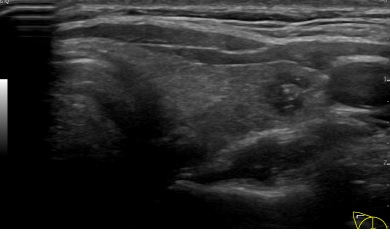

상기환자 갑상선 양성추정결절 추적관찰하시는 30대 후반 여성분으로 갑상선 초음파 시행후 의심스러운 갑상선 좌엽 결절 세포검사 진행후 갑상선암으로 진단되었습니다